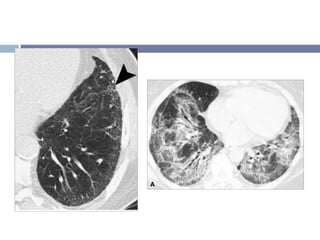

TCAR Vidrio despulido (100%) Opacidades reticulares (+ 30%) Áreas de consolidación   (40-70%)

Otros signos radiológicos Engrosamiento de la pared bronquial Bronquiectasias de tracción dentro de las opacidades Patrón en panal de abejas (-25%) “microquístico”